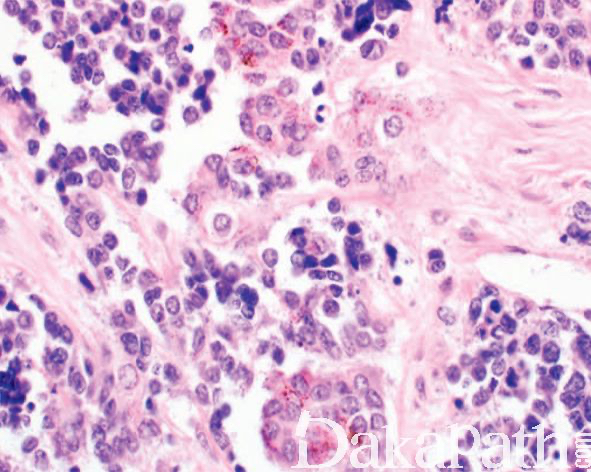

镜下主要可见 2 种细胞,神经母细胞样细胞和上皮性细胞;

神经母细胞样细胞为小的圆形或小立方,核深染、固缩状,多呈巢状或假腺泡状排列;有时该类细胞之间可见神经纤维网样物质;

上皮性细胞体积大,胞质含色素,核呈空泡状,核分裂像罕见,围绕巢状或假腺泡状结构周围;

细胞巢之间可见致密的纤维结缔组织,位于颅面部的肿瘤常可见到骨小梁浸润;